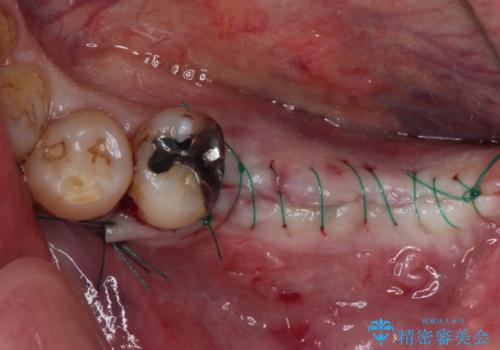

インプラントにはストローマン社のSLActiveを使用し、埋入から補綴までおよそ3か月と、短期間で治療を進めることができました。

- 外科手術のため、術後に痛みや腫れ、違和感を伴います

- メンテナンスを怠ったり喫煙により、お口の中に大きな悪影響を及ぼすインプラント周囲炎等にかかる可能性があります